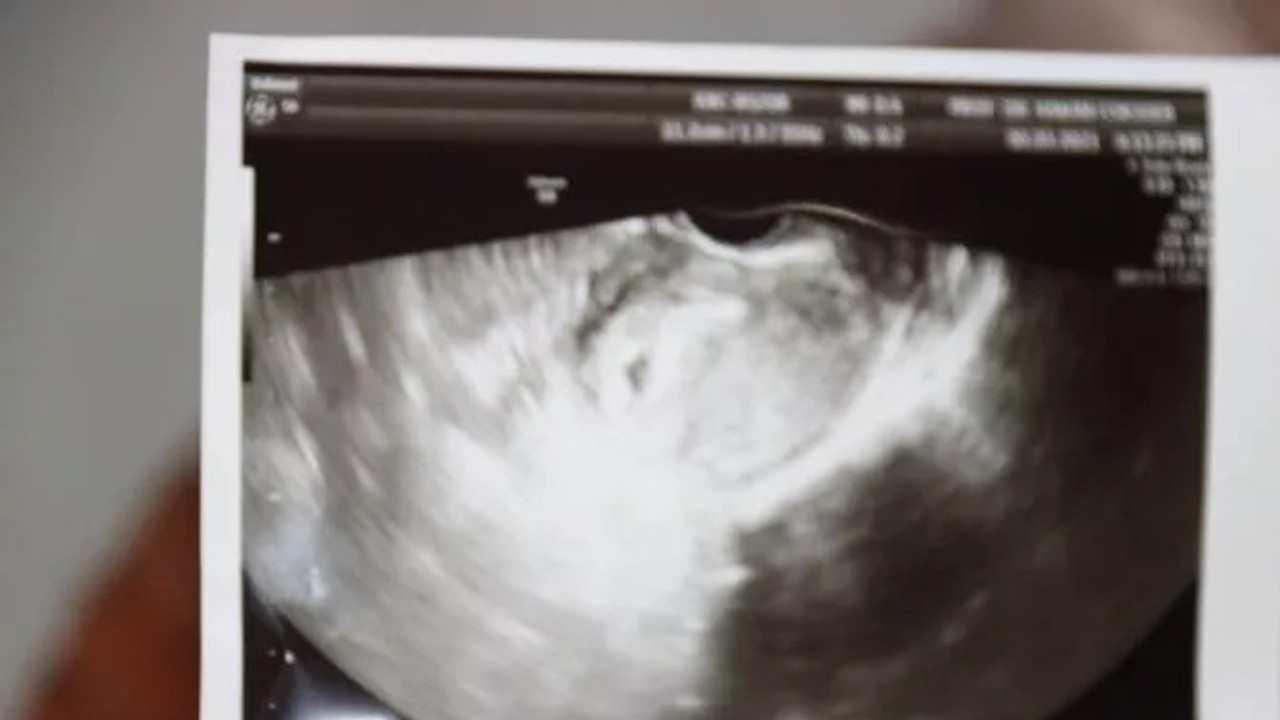

Hastaya daha önce de uygulama yapıldığını ve hiç hücre bulunamadığını belirten Prof. Dr. Hakan Çoksüer, o süreçte tüp bebek uygulamasının da iptal olduğunu söyledi. Prof. Dr. Çoksüer, "Hasta birçok merkezde tedavi almaya çalışmış fakat sperm bulunamadığı için tüp bebek uygulaması yapılamamış. Biz de, hasta kliniğimize geldiğinde ilk önce sperm detoks tedavisi yaptık. Özellikle spermin daha iyi gelişim sağlayabilmesi için. Destoks tedavisinden sonra biz tüp bebek yapmaya karar verdik. Çünkü hastaya baktığımızda hastanın hiç spermi yoktu. Tüp bebek yaptıktan sonra yumurtaları aldığımız esnadan sonra mikro TESE uygulaması yaptık. Mikro TESE'de öncü hücreleri aldıktan sonra Rosi uygulaması yöntemi uyguladık. Rosi yöntemi Japonya’da uygulanmaya başlanmış. Artık son yıllarda bizim ülkemizde yapılıyor. Biz de kendi kliniğimizde Rosi yöntemiyle tüp bebek uygulaması yaptık. Rosi yöntemi sonrası gebelik elde ettik. Tabi bu esnada hastamızın stresi fazla olduğu için biz akupunktur tedavisi yaptık. Akupunkturla hem stresi azalttık hem yumurta kalitesini artırdık. Sonrasında biz transferimizi gerçekleştirdik. Embriyoların gelişimi iyi oldu ve embriyolarımız beşinci güne kadar gitti. Çünkü burada embriyoların da kaliteli olması bizim açımızdan önemli. Transfer sonrası sonucumuzu aldık. 12’nci günde de test yaptığımızda test sonucu pozitifti. Bugün de ultrasona baktığımızda gebelik kesesi gördük. Gebelik kesesini gördükten sonra hasta gözlerine inanamadı. Çünkü hastaya daha önce, hiç hücre olmadığı için imkansız olduğu söylenmiş. Doğru tedavi, doğru merkez, doğru uygulama başaranın ana anahtarıdır" dedi.